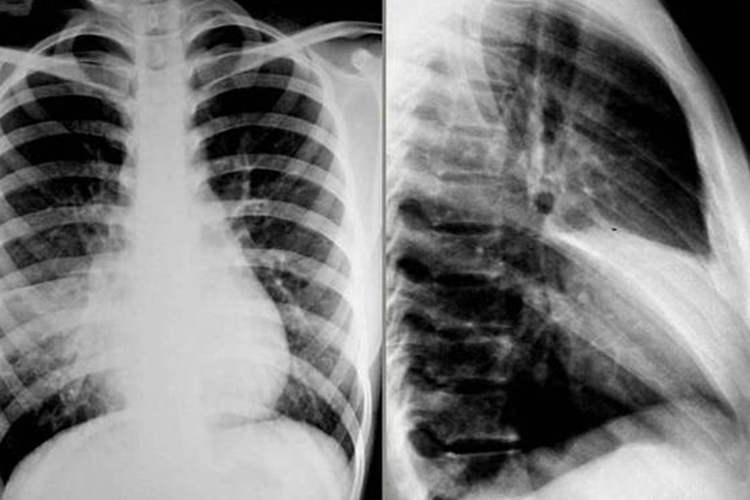

肺叶不张

肺叶不张的X线表现为肺叶体积缩小,密度增高,肺血管、肺门及纵隔不同程度向患侧移位,邻近肺叶可出现代偿性肺气肿。

肺段不张

较少见,正位及侧位一般表现为基底在外、尖端指向肺门的三角形密度增高影,肺段体积缩小,右中叶内侧段不张则特殊,正位呈基底向内与右心缘重叠、尖端向外的三角形密度增高影。